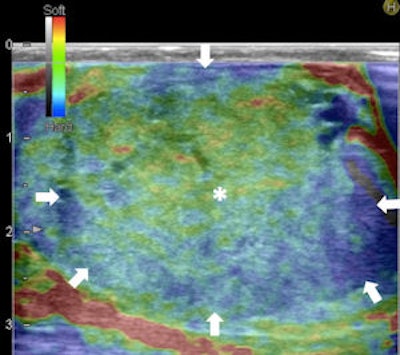

Top left: Grayscale ultrasound image of the testes showing a large isoechoic nodule (40 x 20 mm) compared with the testicular tissue (arrows). Top right: Color Doppler showing peripheral and central vascularization of the nodule, suggesting a malignant lesion. Bottom left: RTE of the nodule showing a large central strain area (mainly an intermediate elastic pattern displayed in green) (*) surrounded by a no-strain rim (the peripheral part of the lesion is blue) (arrows). This pattern, that the researchers suggested calling "score 3-inverted" (the opposite of the known color-coded score 3 reference of Itoh et al) seems to be related to the Leydig tumors. Bottom right: Gross specimen of the testicle. Histological diagnosis of the nodule was Leydig tumor, consisting of cells with abundant cytoplasm without interstitial fibrous stroma; the slow growth of the tumor induces sclerohyalinosis at the periphery. The tumor's macrostructure explains the RTE pattern.Because clinical examination has its drawbacks, ultrasound has become the imaging technique of choice for evaluating scrotal abnormalities -- with the primary function of ultrasound being the diagnosis of a testicular mass to distinguish intratesticular from extratesticular location. Most extratesticular masses are benign, but intratesticular ones are malignant.

Color-coded elastographic score (SC1 to 5) suggested by Itoh et al for breast disease and modified by Goddi et al for testicular lesion assessment. 1 indicates strain for entire lesion. 2 indicates strain in most of the solid lesion with some areas of no strain. 3 indicates strain at the periphery of the solid lesion, with no strain at the center. 3-inverted indicates strain at the center of the solid lesion, with no strain at the periphery of the lesion. 4 indicates no strain in the entire lesion. 5 indicates no strain in the entire solid lesion and surrounding area. If scored between 1 and 3, lesion would be benign; if scored 3-inverted, lesion would be considered suspect for a Leydig tumor; if scored 4 or 5, lesion would be considered malignant.

The Leydig tumors in the study were slightly hyperechoic compared with the surrounding tissue and showed mainly an elastic pattern at RTE. At histology, Leydig tumor consists of polygonal cells with abundant, eosinophilic cytoplasm, solid, sheet-like pattern without interstitial fibrous stroma. The progressive growth of this type of tumor induces sclerohyalinosis of the surrounding glandular tissue detectable as a stiff blue rim at RTE.

"We suggested introducing a further score value (score 3-inverted) -- never described before -- which corresponds to a specific histological pattern," Goddi said in an interview with AuntMinnieEurope.com.

The RTE appearance for Leydig tumors seems the exact opposite of the known score 3 reference, which is why the researchers suggest an additional score.